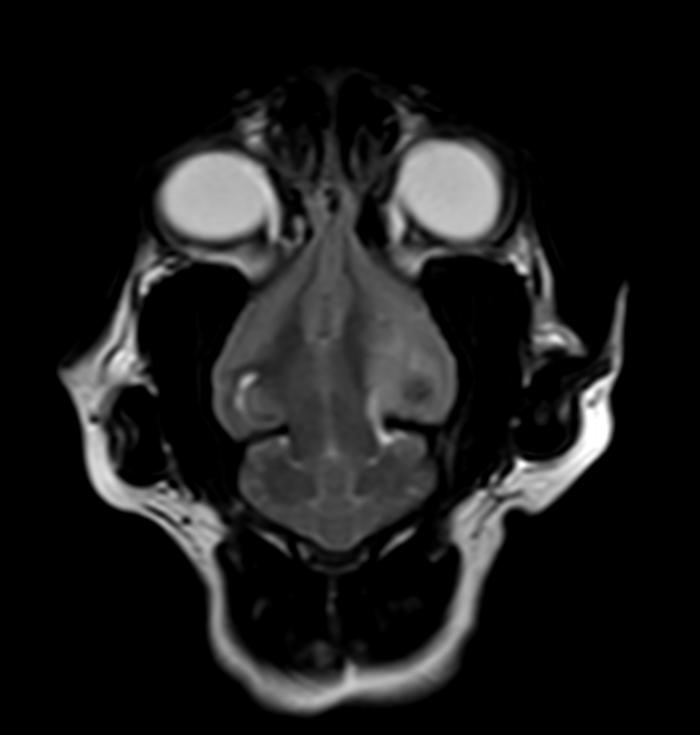

Cultivo: en ambas muestras existe crecimiento moderado de Pasteurella multocida con antibiograma sensible a todos los antibióticos testados (Tabla 1). Por ello, se alarga la pauta con ambos antibióticos hasta alcanzar 15 días en el caso de la doxiciclina y 45 días en el caso del trimetoprim-sulfametoxazol. Una vez finalizada la pauta antibiótica, se da el alta (Figura 3).

Durante los 6 meses posteriores, la gata no ha presentado signos nasales ni neurológicos.